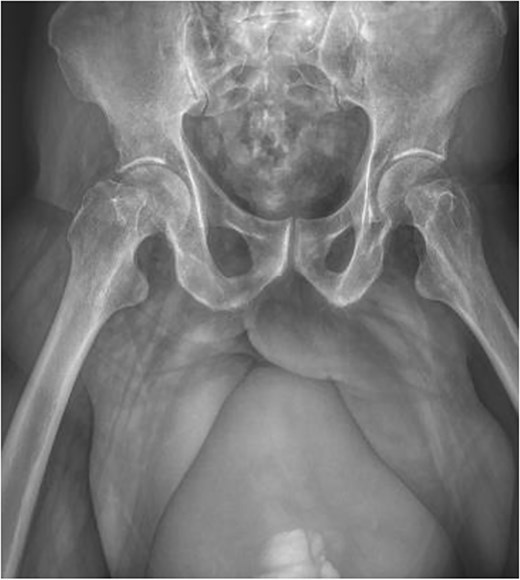

On admission, physical examination revealed a tense bulge (25 × 22 cm) in the right inguinal region, with moderate pain on palpation and no changes in coloration or temperature (Fig. 1a and b). Laboratory tests reported leukocytes 13.6 10 × 3/μL, neutrophils 88.9%, hemoglobin 14.1 g/dL, hematocrit 40.9%, platelets 344 000 10 × 3/μL, glucose 102 mg/dL, urea 147.7 mg/dL, creatinine 5.30 mg/dL, sodium 130 mmol/L, potassium 4.5 mmol/L, and arterial blood gas without alterations, lactate 1.2 mmol/L.

Clinical image of a bulge in the right inguinal region, approximately 25 × 22 cm in size, exacerbated by urine retention, without changes in coloration (a), and the same right inguinal bulge demonstrating how the size of the bulge increases with urine retention (b).